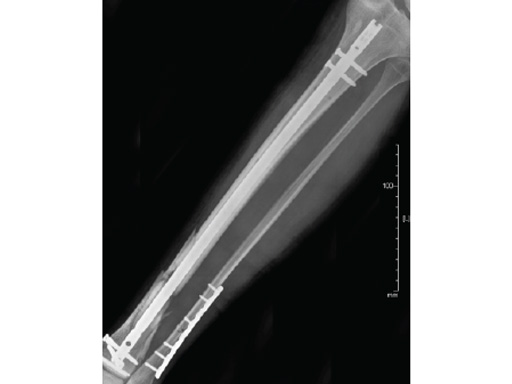

Case 2: Grade II open distal tibial fracture in a polytraumatized 52-year-old man.